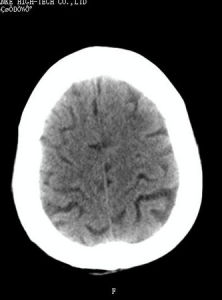

腦電圖、CT可以做出相應的診斷。鑑別

⑴ 淺昏迷:意識大部分喪失,對周圍事物及聲光刺激均無反應,但對強烈的刺激有反應,病人各種反射存在,有大小便失禁。

⑵ 深昏迷:意識全部喪失,對外界各種刺激均無反應,各種反射消失,全身肌肉鬆弛。